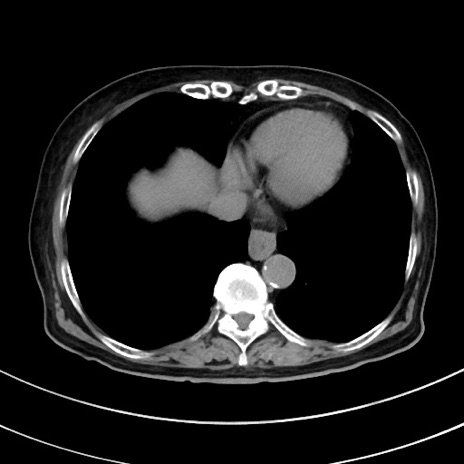

症例33(横断像)

【症例】70歳代 女性

【主訴】心窩部痛

【現病歴】延髄病変の精査・加療にて神経内科入院中。本日より心窩部痛あり。

【身体所見】右下腹部を中心に圧痛と反跳痛あり。

【データ】WBC 10900、CRP 0.02